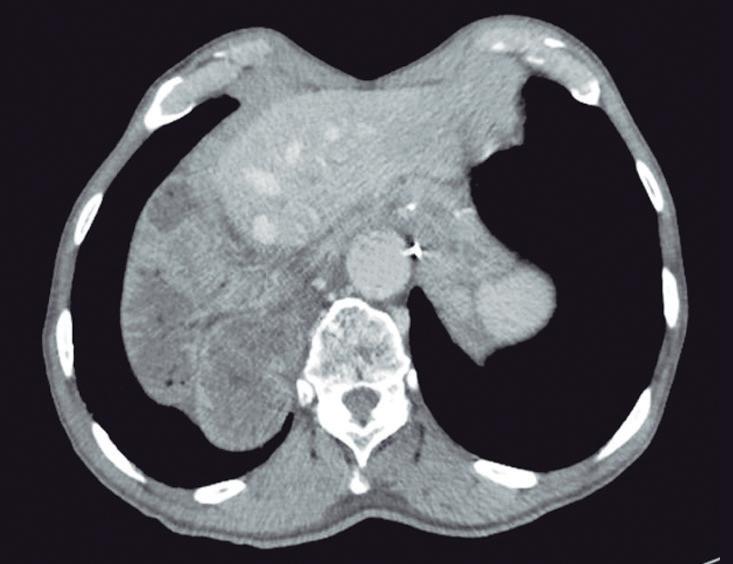

Evaluación endoscópica e histológica

La endoscopía superior es un procedimiento fundamental para el diagnóstico, la evaluación de la respuesta al tratamiento y el monitoreo a largo plazo de la actividad de la EEo. Los hallazgos endoscópicos típicos incluyen edema (reducción de vascularidad), anillos esofágicos fijos, exudados blancos, surcos longitudinales, estenosis, estrechamiento de la luz esofágica, friabilidad de la mucosa (mucosa en papel crepé) y una consistencia firme de la mucosa al realizar biopsias (signo de “tracción" o "resistencia”) en pacientes con fibrosis (Figura 1). Estos hallazgos no son patognomónicos y no constituyen un criterio diagnóstico; sin embargo, cuando se evalúa de forma cuidadosa, en la gran mayoría de los casos se pueden observar.19-21

En el panel A se observa un esófago con edema difuso y pliegues longitudinales; en el panel B se aprecia edema con pliegues y exudados blanquecinos; en el panel C se evidencia un estrechamiento luminal acompañado de anillos esofágicos y exudados; y en el panel D se muestra un desgarro mucoso posterior a la dilatación con bujía de Savary, hallazgo esperado tras este procedimiento terapéutico.

Figura 1. Características endoscópicas de la esofagitis eosinofílica